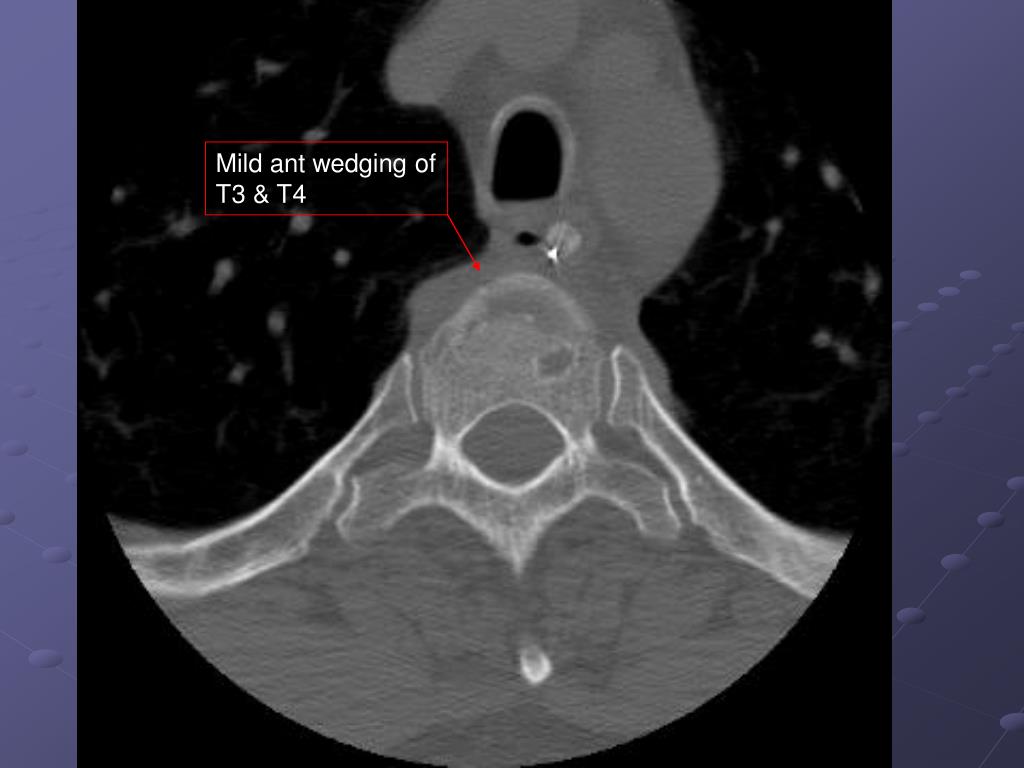

18. Case 3 • 50 yo male again 10-12 foot fall off ladder while putting up Christmas lights (dangerous hobby)

19. Mild ant wedging of T3 & T4

20. Mild ant wedging of T3 & T4